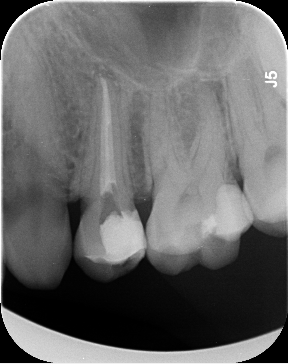

Dantų kanalų gydymas